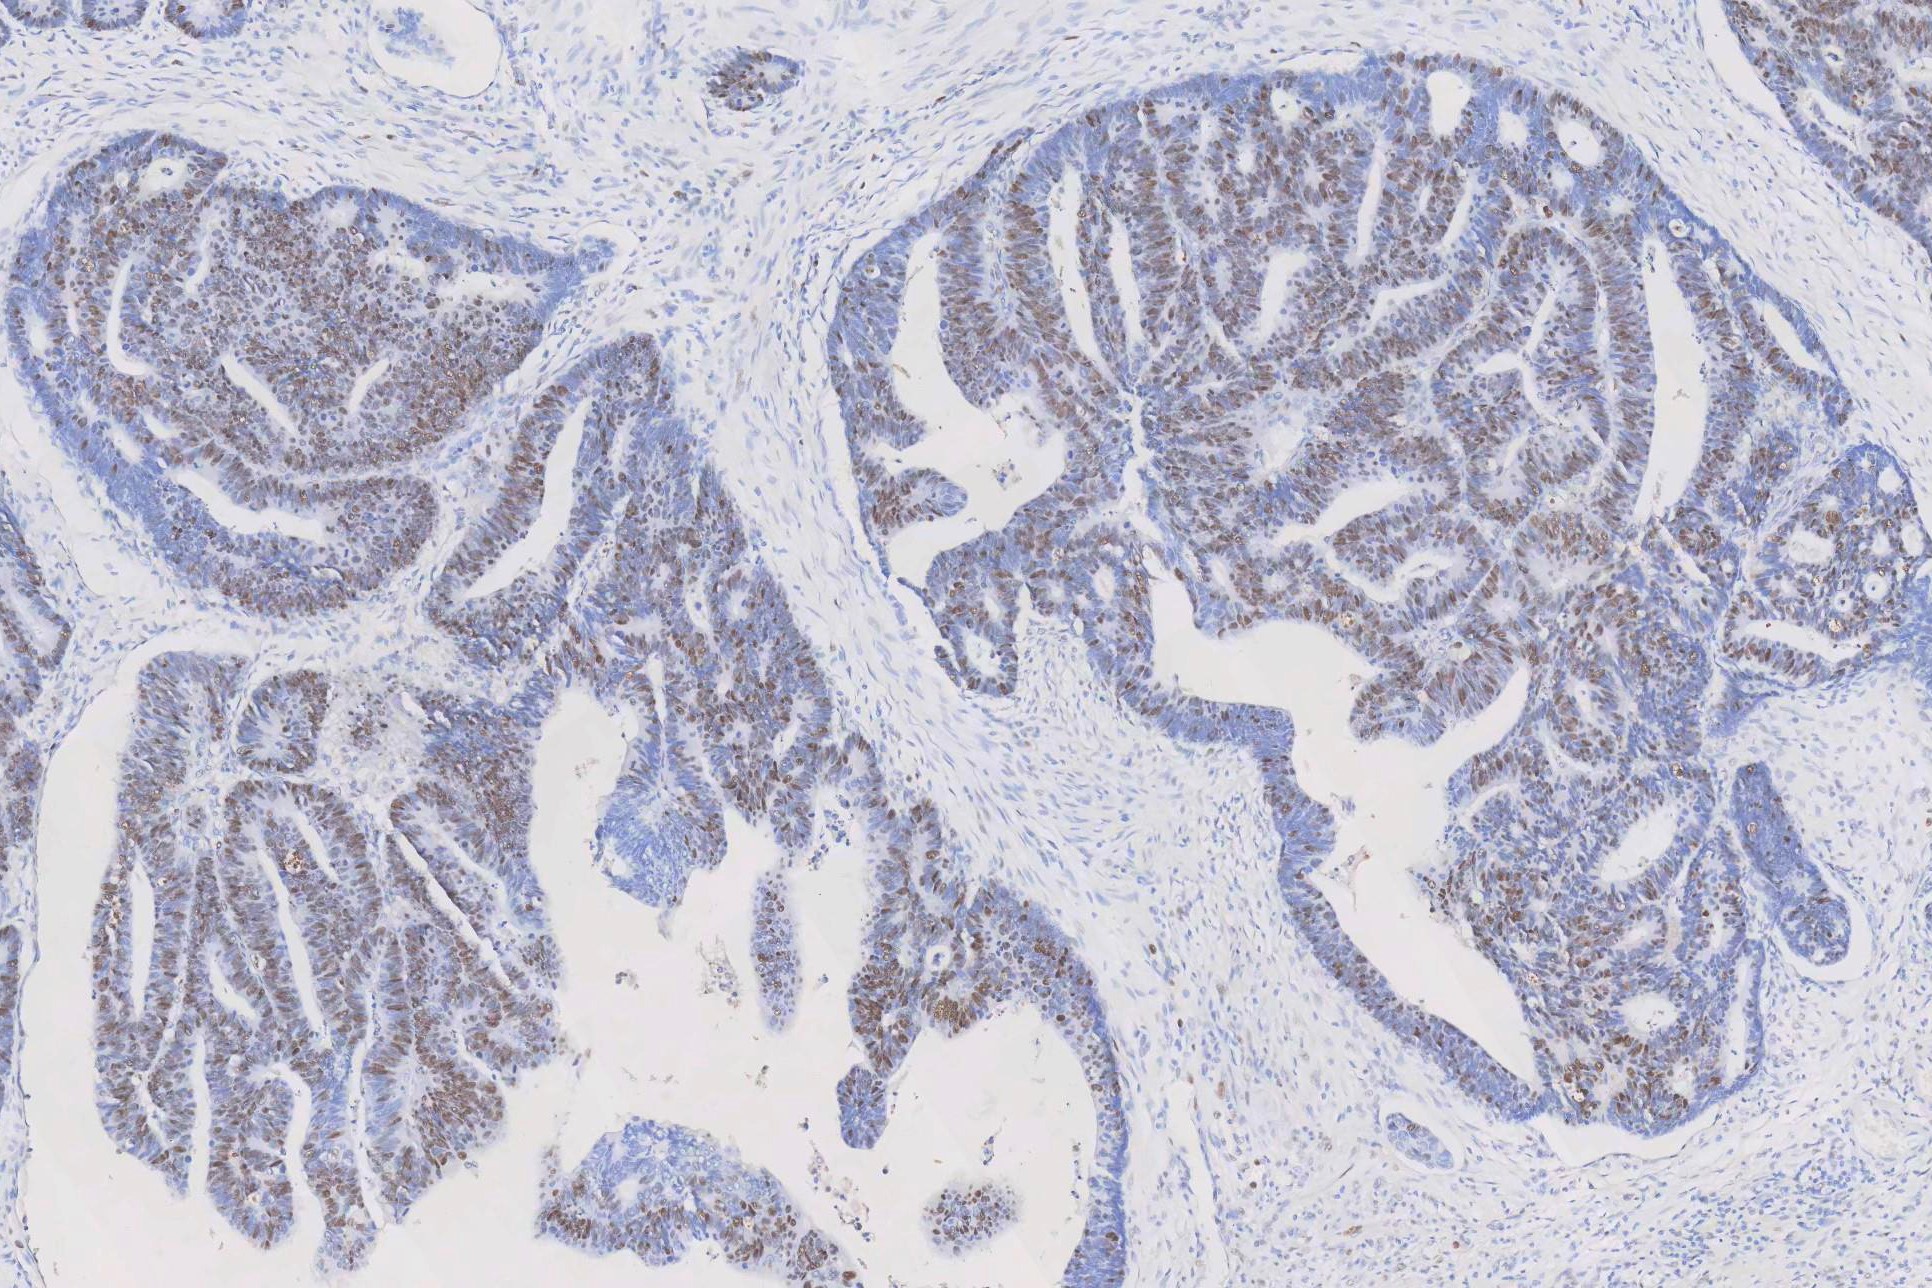

IHC analysis of PCNA using anti-PCNA antibody (MA1083). PCNA was detected in a paraffin-embedded section of human rectal cancer tissue. The tissue section was blocked with 5% BSA. The tissue section was then incubated with 1μg/ml mouse anti-PCNA Antibody (MA1083) overnight at 4°C. Peroxidase Conjugated Goat Anti-Mouse IgG was used as a secondary antibody and incubated for 30 minutes at 37°C. The tissue section was developed using the HRP Conjugated Mouse IgG Super Vision Assay Kit (Catalog # SV0001) with DAB as the chromogen.